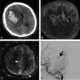

Distal clavicle defect